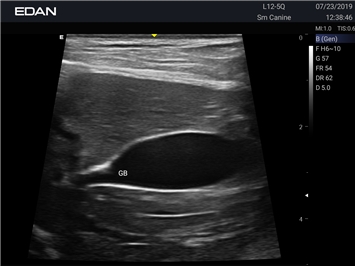

EDAN Acclarix AX3 VET

Ветеринарный ультразвук одним нажатием. Система Acclarix AX3 VET разработана с целью обеспечить бескомпромиссную производительность по доступной цене. Наличие уникальных двойных разъемов и двойных аккумуляторов в легком корпусе массой 4,5 кг из магниевого сплава позволяет системе Acclarix AX3 VET удовлетворять все потребности ветеринарных исследований, сохранив низкую стоимость.

EDAN Acclarix AX3 VET - это компактная ультразвуковая система, специально разработанная для ветеринарной практики, сочетающая высокую производительность с доступной ценой.

• Революционная платформа с превосходным разрешением для глубоких структур

• Специальные настройки для исследования животных разных видов